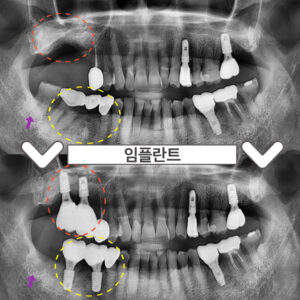

부천시청역치과 임플란트 뼈 이식이 필요하다면? 안녕하세요 😀 이로운 치료를 선사하는 서울이로운 치과입니다. ^^ 임플란트를 하고 싶어도 잇몸뼈가 충분하지 않아서 동네병원에서 하지 못하는 경우가 종종 발생하는데요. 오늘은 잇몸뼈가 없어서 임플란트를 할 수 있을지 고민하시는 분들을 위해 ‘뼈가 없어서 임플란트 치료가 가능한지 모르겠다며’ 본원을 찾아주셨던분의 케이스에 대해 설명드리려 합니다. 🙂 처음 본.원을 더보기…